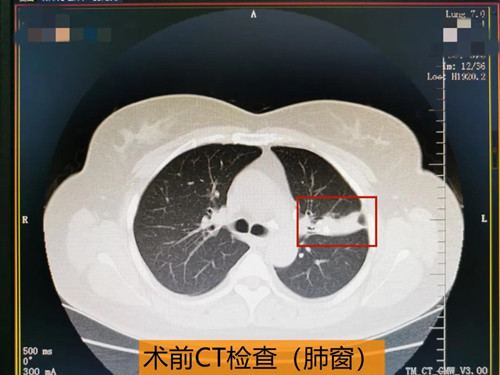

近日,47岁的王女士患上了“支气管结石病”。起初王女士自觉左侧胸痛,伴活动后心慌、气短,以为是心脏出了问题,于是到某医院心内科就诊,心电图提示心动过速,肺CT检查显示左肺上叶慢性炎症并局部钙化,原因不详。医生为她开了治疗慢性支气管炎的中成药,王女士回家口服了一段时间,胸痛等症状没有改善,这让王女士苦恼不已,这时有朋友建议她到秦皇岛军工医院呼吸内科就诊。

王女士来到秦皇岛军工医院后,呼吸内科主任张丽娜结合王女士的临床表现及肺CT检查结果,考虑患者左肺上叶存在气道狭窄及阻塞性肺炎,炎症波及到胸膜,所以出现了左侧胸痛,同时因阻塞性肺炎的存在,会有肺功能下降,从而出现活动后胸闷、气短等症状,张主任建议王女士做支气管镜检查明确病因以及对症治疗。